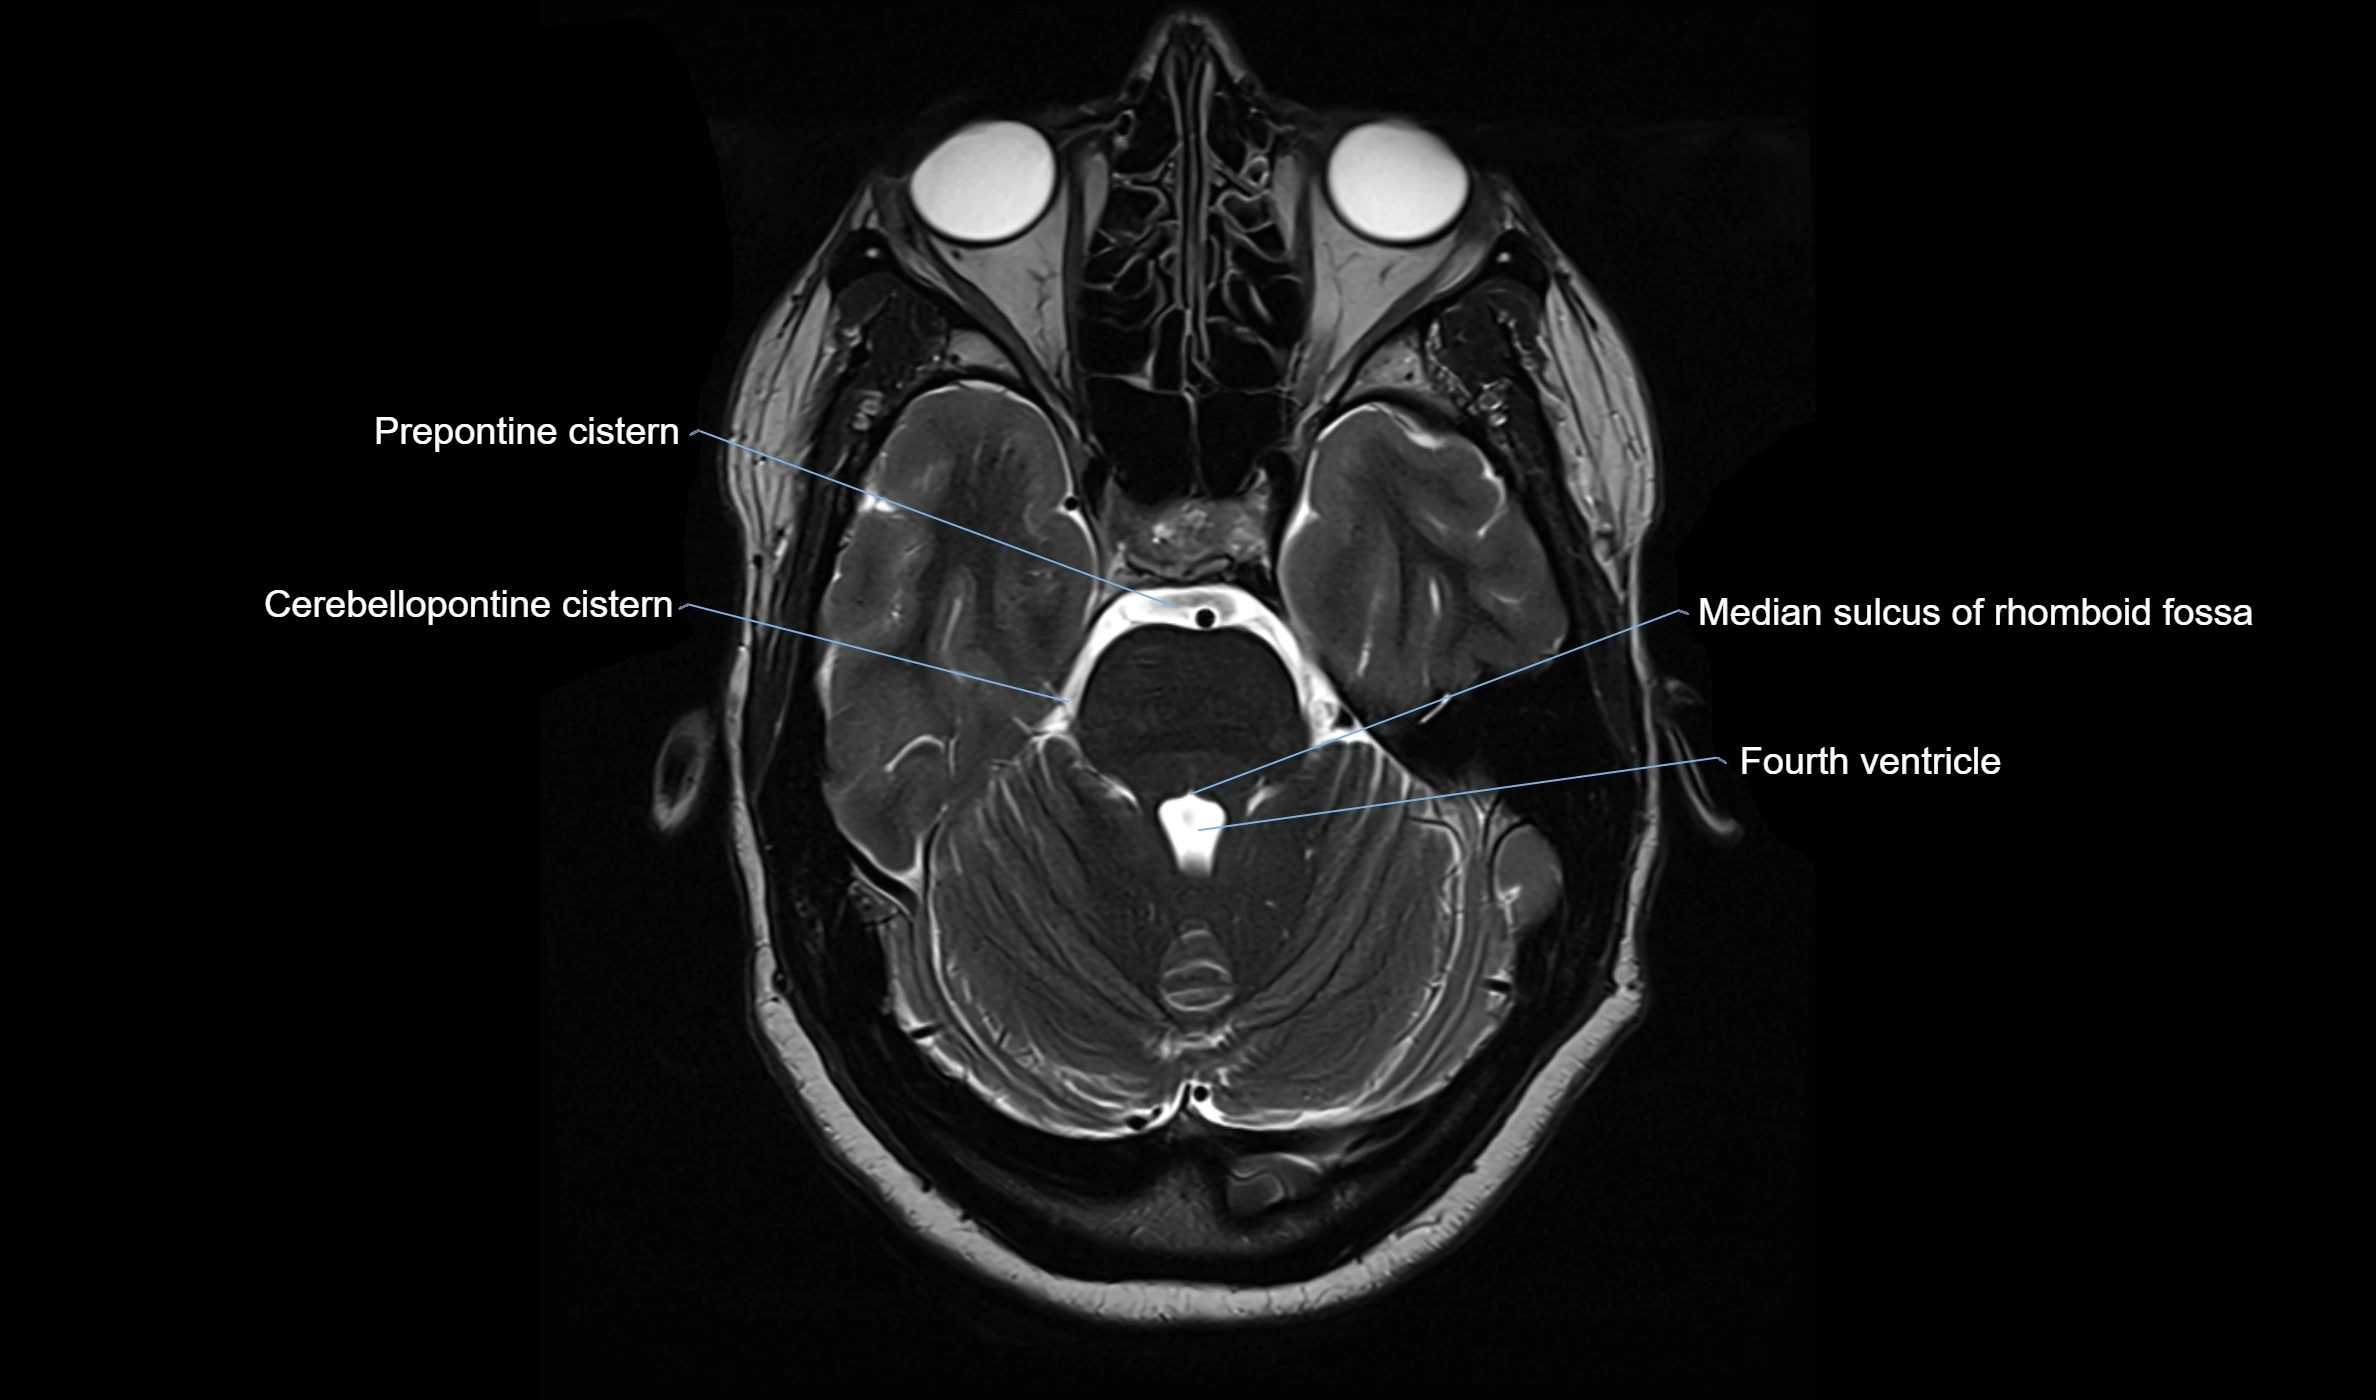

MRI images

image